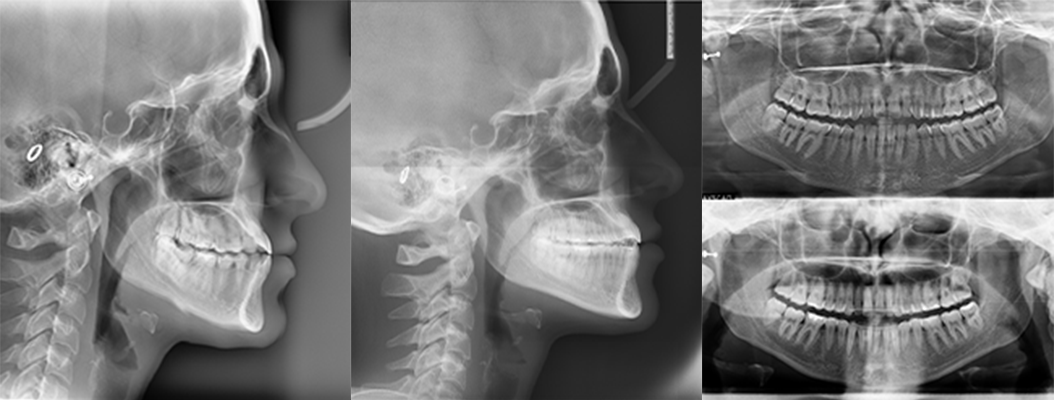

A 22-year-old female patient presented with a Class III malocclusion. She does not like her own profile. Her facial profile was straight with a slightly retrusive maxilla, the upper incisors were within normal inclination, and the lower incisors were retroclined. Bolton discrepency is on mandible for 6 teeth. A retruded upper lip and a normally positioned lower lip were noted. There was also a marked lack of midface support, and the constricted dental arches resulted in a narrow smile and pronounced dark buccal corridors.

Initial leveling in the maxillary arch was carried out with a 0.014 CuNiTi archwire. This was followed by a 0.018 CuNiTi wire, with stoppers positioned mesial to the molars and activated to provide protrusion of incisors. The mandibular arch was then bonded and initial alignment was achieved with a 0.014 CuNiTi wire, then both jaws are progressing to 0.014 × 0.0275 CuNiTi and subsequently 0.018 × 0.0275 CuNiTi for torque control.

Finishing was completed with a 0.018 × 0.0275 TMA archwire in conjunction with Class III elastics.

At the end of treatment, the patient’s occlusion was corrected to Class I molar and canine relationships with a physiological overjet and overbite. Irregularities in both arches were eliminated, arch forms were coordinated, and incisor torque was effectively controlled to position the roots centrally within the alveolar bone, enhancing stability. Satisfactory intercuspation was achieved in both the anterior and posterior segments, with maintenance of midline coincidence and periodontal health throughout treatment. The case was finished and transitioned into the retention phase using fixed retainers in the maxillary and mandibular anterior regions.